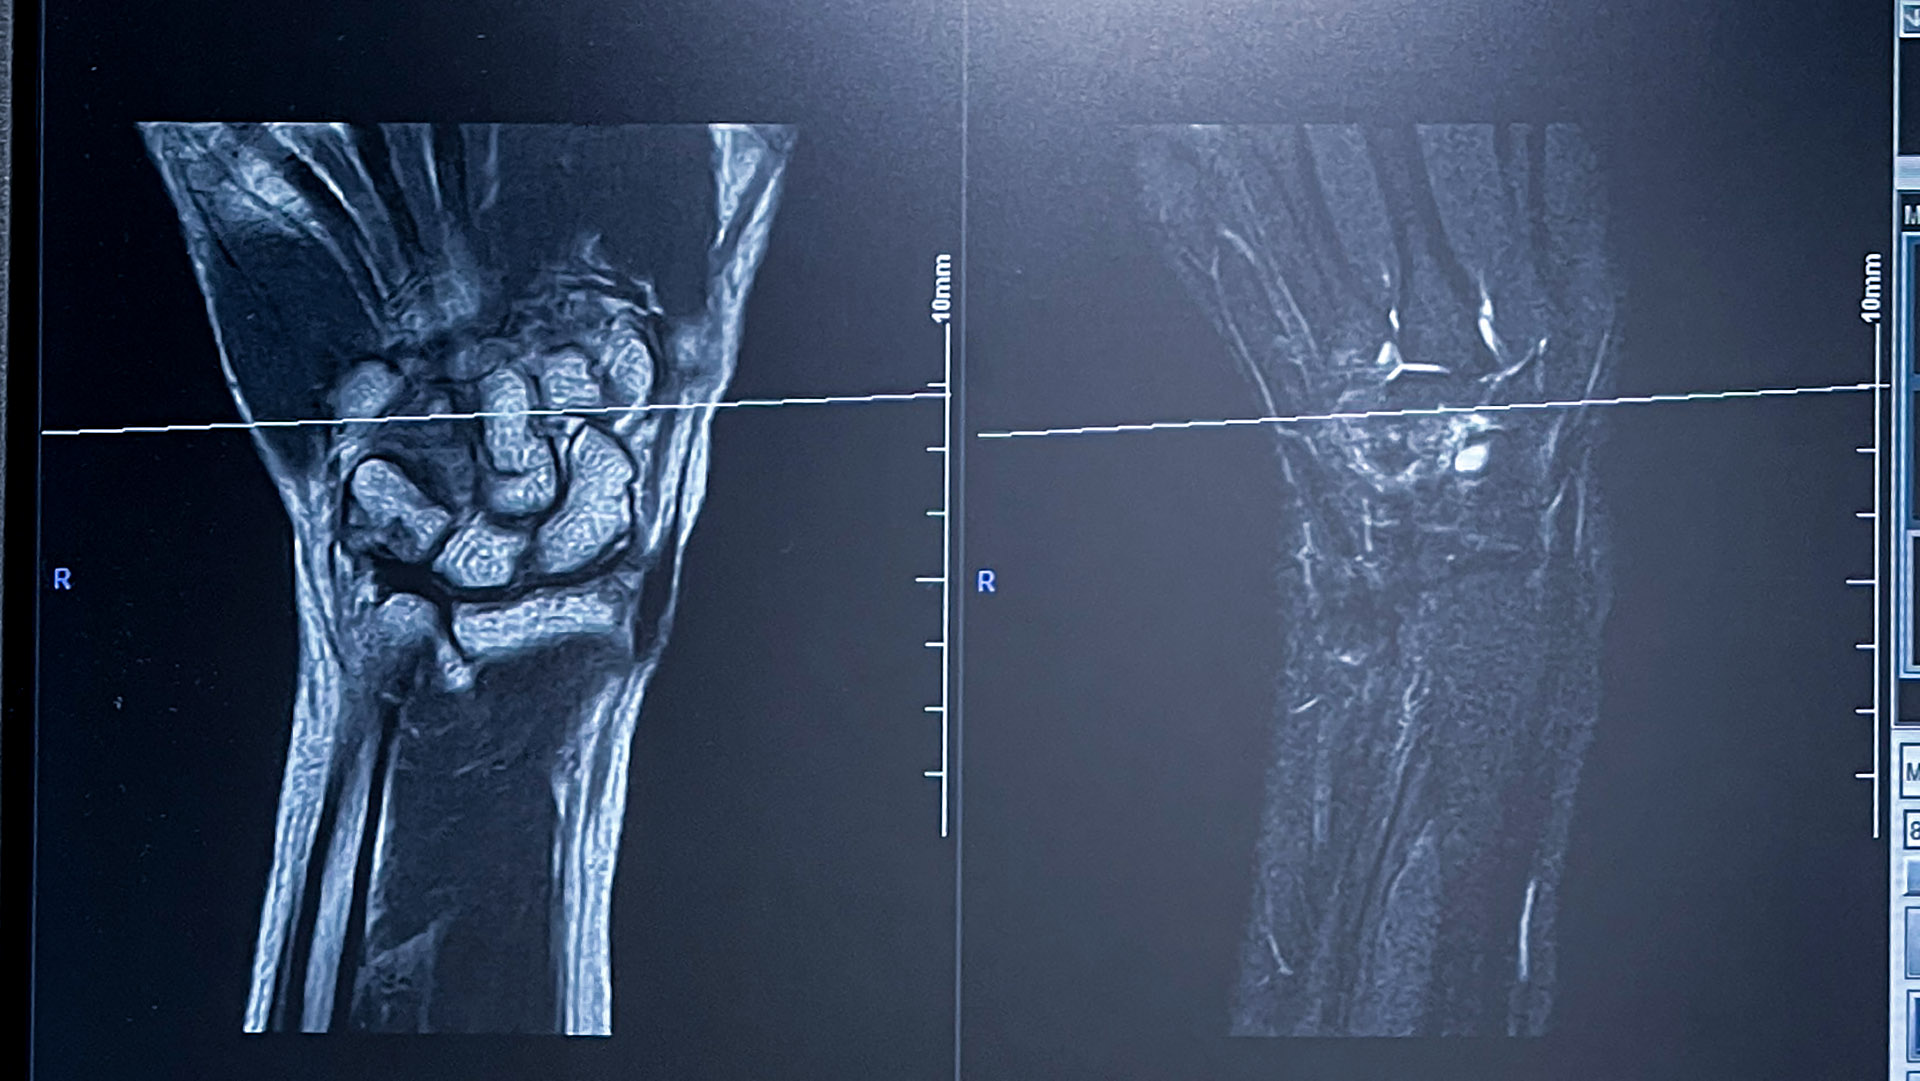

整形外科の先生が大事をとってということで

近所のMRIがある病院に紹介状をかいてくれて

始めて MRIを体験してきた。

左手を広げ 思いっきり伸ばしスーパーマンのような姿勢で横になり 10分ほど固定。。

地場の音という不快な騒音のなか 撮影で来たのがこの画像。